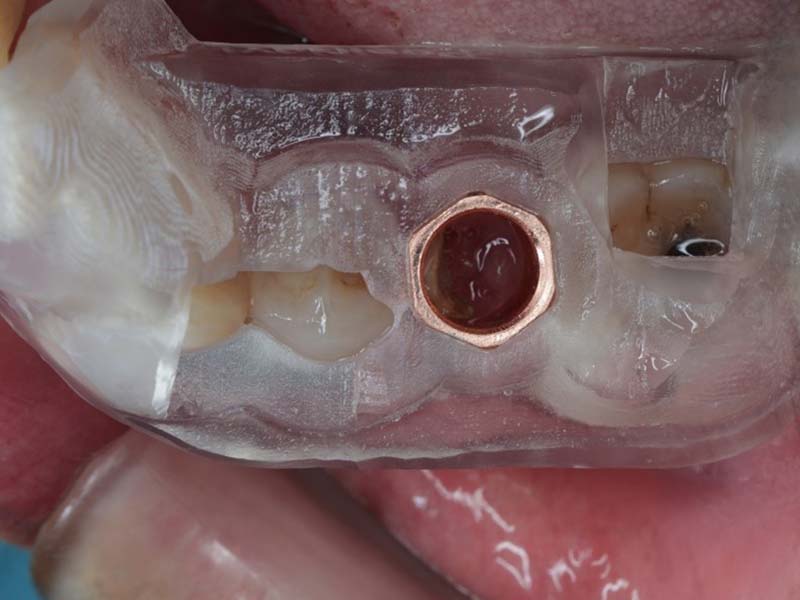

使用數位手術導板精確定位植體位置,確保角度與深度正確,提升植牙成功率